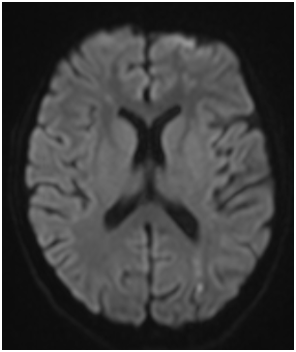

A 14-year-old female presented with subacute onset of random, unintentional movements involving the neck, trunk, limbs as well as facial muscles. The movements were sever enough to interfere with mobility. Otherwise she did not have any systemic complaints. Had no history of a recent infectious illness and did not use any medication. Her past and family history was unremarkable. On examination, she was alert, fully oriented with intact cognitive functions. The movements were noted as involuntary, rapid and purposeless generalized movements. She could not control it and had difficulty stabilizing her head. Auscultation revealed pansystolic murmur over the apex. She had no skin lesion, joint tenderness or swelling. Blood investigations showed normochromic normocytic anemia with thrombocytopenia (Hb: 8g/dl, MCV: 80 fl, WBCs: 4.5×10⁹ Platelets: 84×10⁹). Had normal renal and liver functions. Coombs test was positive, ANA and anti-dsDNA Abs were positive. Furthermore her cardiolipin IgG was positive (36.9 U/ml) and urine analysis shows hematuria (20-30/HPF) and proteinuria (100 mg/dl). Brain MRI demonstrated multiple bilateral old and recent ischemic lesions (Figure 1). Echocardiography show mildly thickened mitral valve with prolapsed of anterior segments of mitral leaflet & moderate mitral regurgitation.

Figure 1 (A & C) FLAIR and (B & D) Diffusion-weighted images of the brain showing multiple small infarctions at different ages (old and recent) involving the deep white matter of both cerebral hemispheres. The acute infarcts show diffusion restriction on B & D, while old infarctions show low signal on FLAIR images with surrounding gliosis.